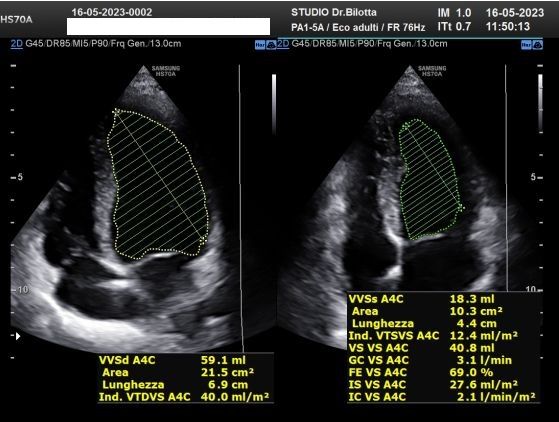

Foto e video